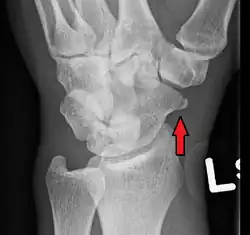

-

A subtle scaphoid fracture -

A more obvious scaphoid fracture on a scaphoid view X ray -

Radiolucency around a 12 days old scaphoid fracture that was initially barely visible.[13]